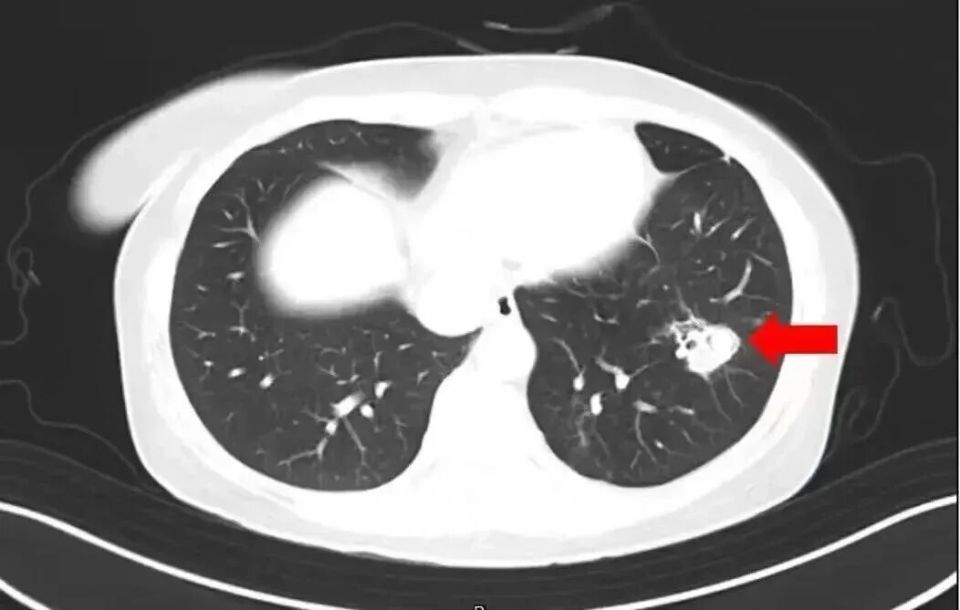

• 2025年1月,江苏扬州的张大爷为迎接春节开始大扫除,清扫过程中不慎吸入大量灰尘和霉菌孢子,导致哮喘发作。张大爷随即服用了常备的哮喘治疗药物,可症状反而逐渐加重。经检查,张大爷的肺部出现感染,确诊为肺曲霉病。

北京佑安医院感染综合科主任医师李侗曾介绍,对于免疫力低下的人,吸入了这些真菌,就会发病引起肺部的病变——曲霉肺炎因为它是通过呼吸道感染的,进入血液后是可以扩散到全身。大脑因为血供最丰富,所以也是真菌最容易侵犯的器官。